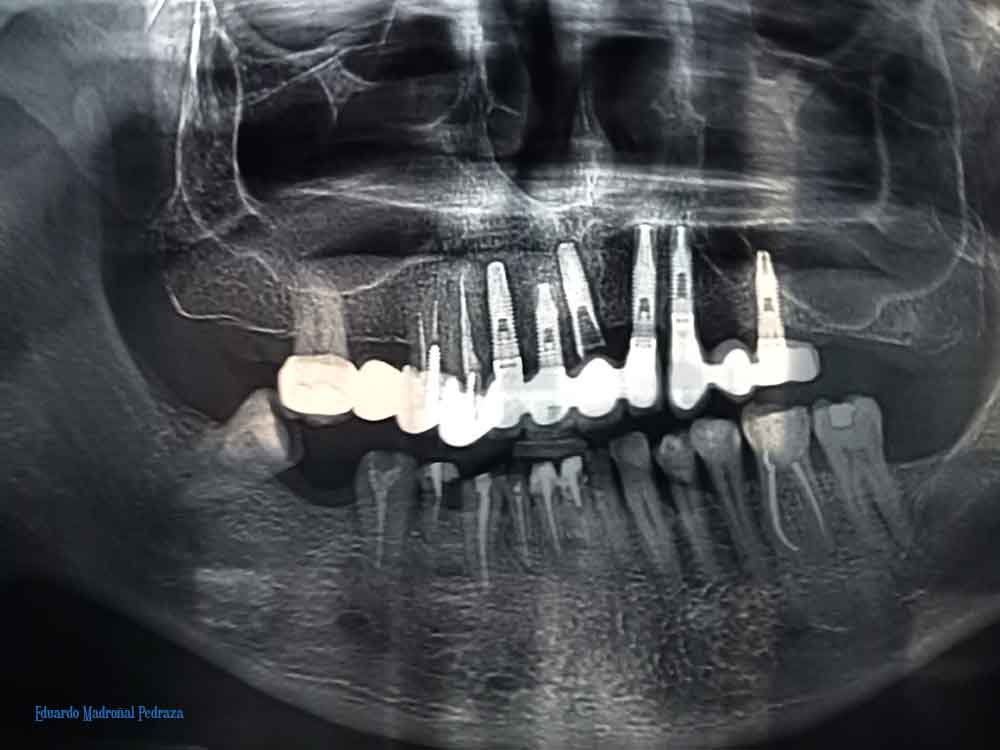

Y el titanio no es ya sólo química/ ni la revolución es ya un objetivo titánico/ porque los maseteros se vuelven titánicos/ porque la conciencia así lo exige

Érase un hombre titánico/ porque mordía la vida/ y después la saboreaba/ porque masticaba la vida/ y después la saboreaba/ y sus maseteros/ rompían un tornillo de titanio

A la luz de la luna llena/ los maseteros, ay, rompían/ un tornillo de titanio/ y las mandíbulas se quedaban/ ay, los restos del tornillo/ a la luz de la luna llena/ ay, las hienas, las hienas

Delicada y suavemente/ sigilosa, sinuosamente/ ¡ay!, se desliza el duende/ entre los muy aterradores/ maseteros trituradores/ ¡ay!, se desliza el duende/ entre crecientes/ huesos crujientes/ ¡ay!, se desliza el duende/ entre el quebrado tornillo/ de fatigado titanio/ ¡ay!, se desliza el duende/ delicada y suavemente/ sigilosa, sinuosamente